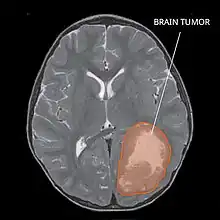

Primitive neuroectodermal tumor of the central nervous system in a 5-year-old

Magnetic resonance image of PNET

Most children that develop primitive neuroectodermal tumors are diagnosed early in life, usually at around 3–6.8 years of age.[2] Symptoms patients present at time of diagnosis include irritable mood, visual difficulties, lethargy, and ataxia.[2] The circumference of the patient's head might also become enlarged and they might be subject to seizures, especially if they have less than one year of life.[2]

Several analysis can be used to determine the presence of the disease. Physical examinations showing papilledema, visual field defects, cranial nerves palsy, dysphasia, and focal neurological deficits are evidences for possible tumor.[2] PNETs can also be spotted through computed tomography (CT) and magnetic resonance imaging (MRI).[2] In images produced by MRIs, an irregular augmentation among a solid mass will indicated the presence of tumor.[3] However, the results of MRIs are usually ambiguous in defining the presence for this specific tumor.[2] In CT scans, the presence of PNETs will be indicated by an elevated density and an increase in volume of the brain.[2] The CT scan can also show calcification,[3] which is present in 41-44% of PNET cases.[2] Since the tumor can be replicated in other parts of the nervous system through the cerebrospinal fluid (CSF), a CSF analysis can also be conducted.[2] A spinal MRI is a fourth type of analysis that is useful in investigating the level of tumor propagation to the spinal cord.[2]